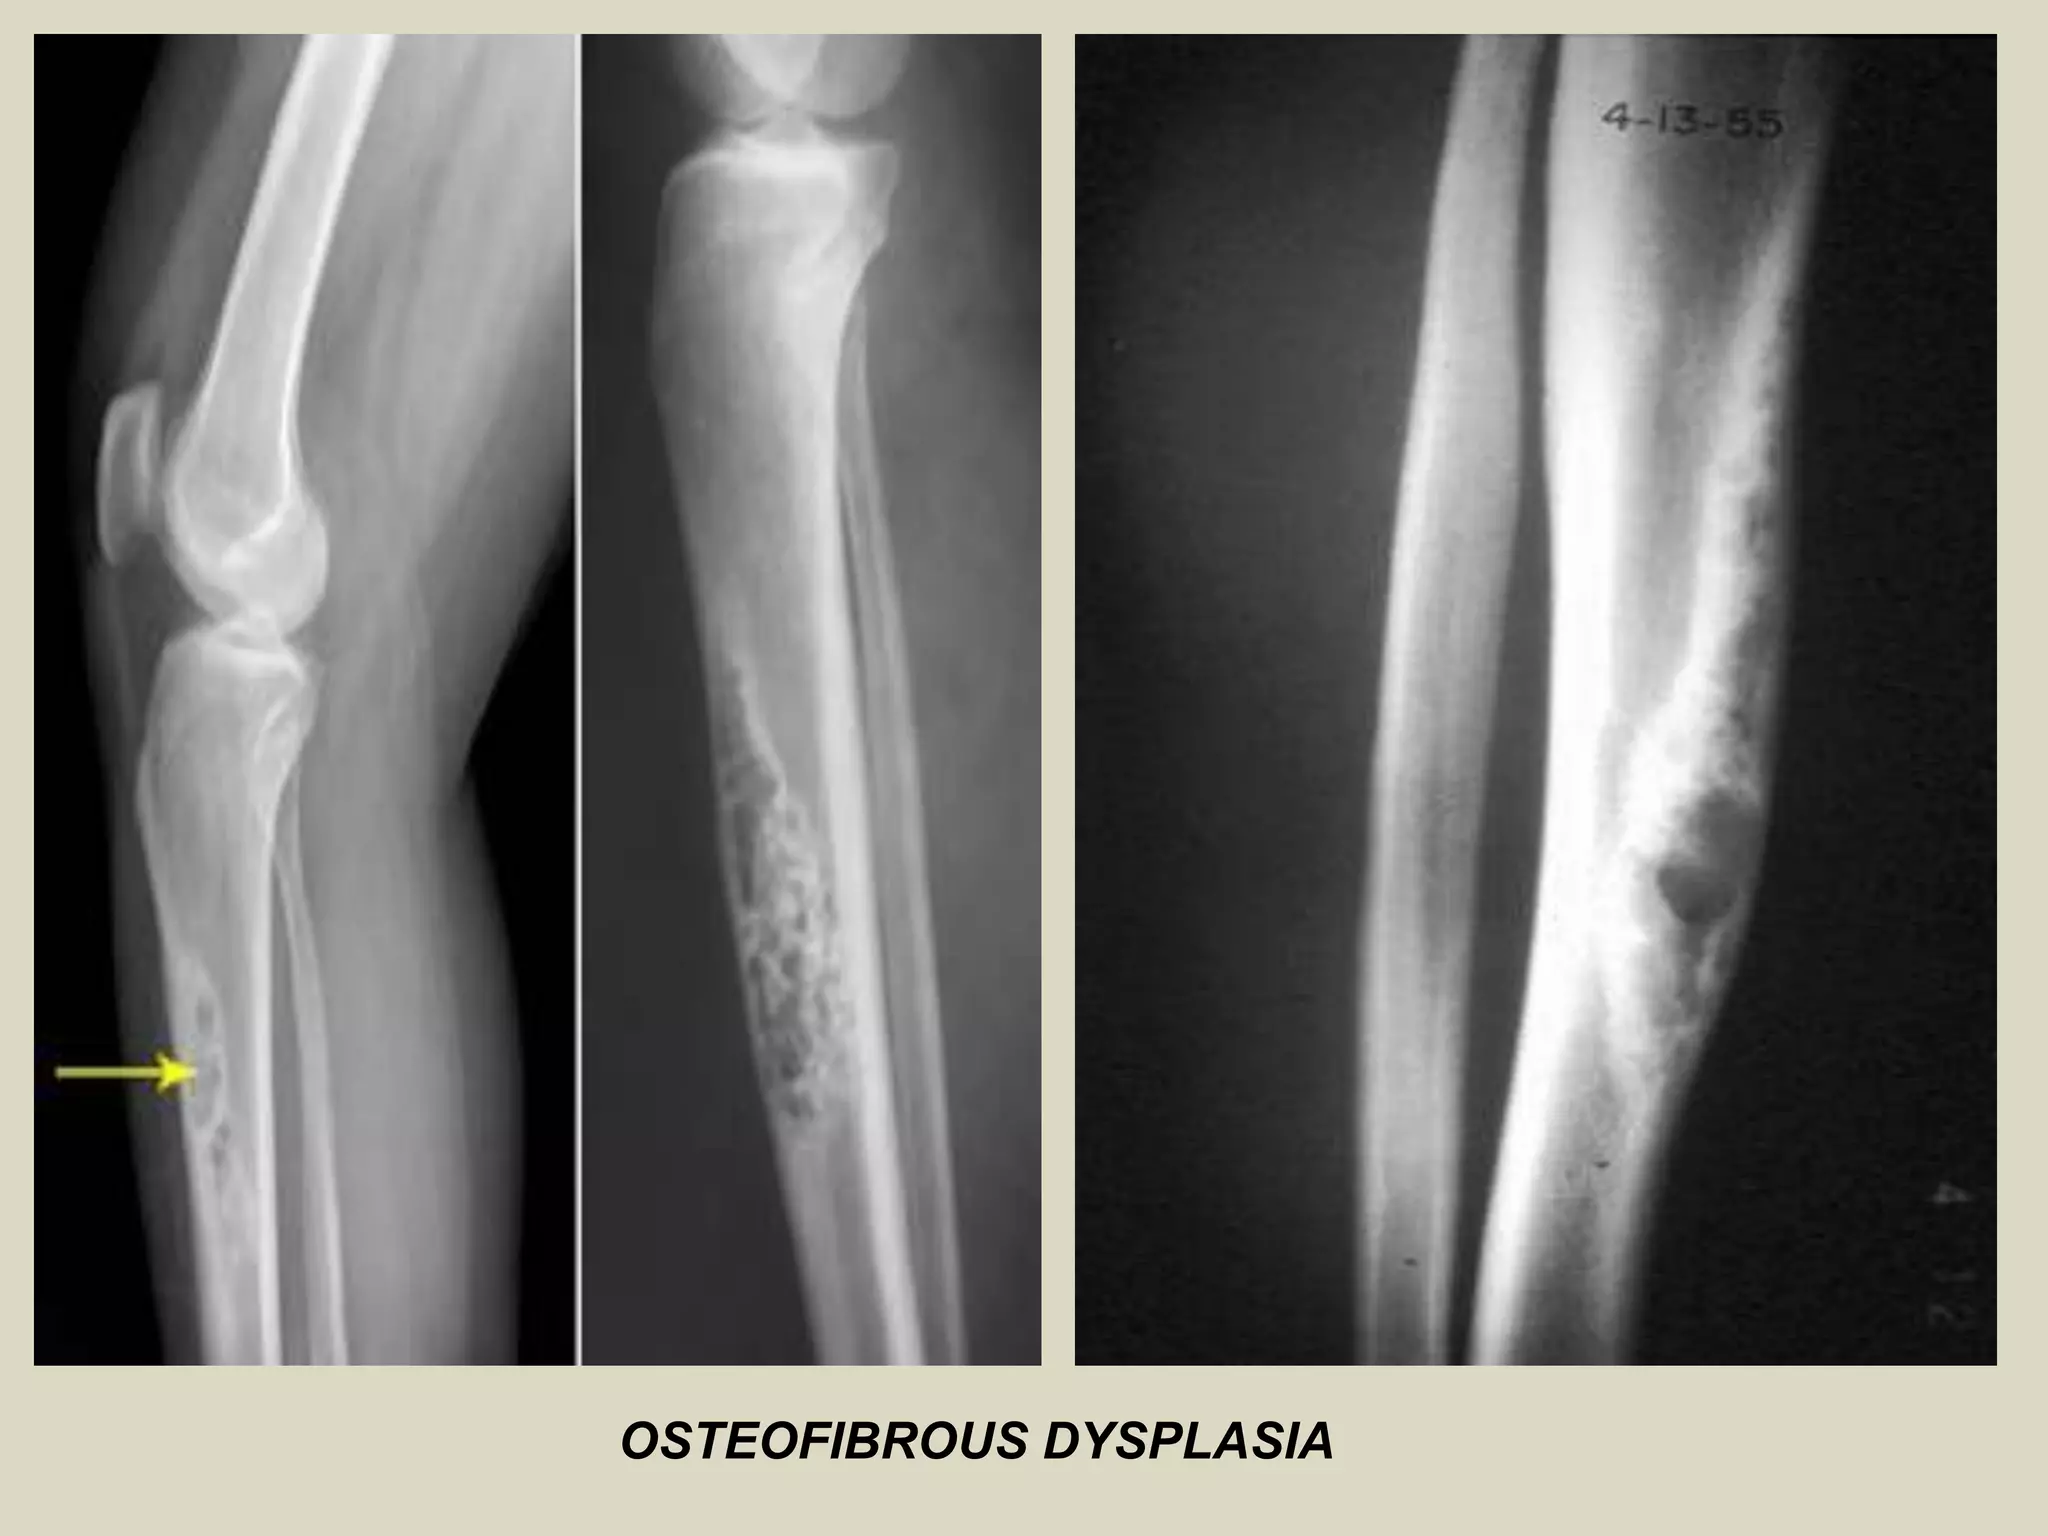

OSTEOFIBROUS DYSPLASIA

Definition:

- Self-limited benign fibro-osseous lesion of bone.

- Involving cortical bone of the anterior mid-shaft of the tibia during infancy and

childhood.

Imaging:

- Well-delineated, Intracortical lucency, surrounded by areas of sclerosis.

- May form as a single lytic lesion, but more commonly forms confluent oval-shaped,

scalloped, saw-toothed or bubbly multiloculated lytic lesions in cortex.

OSTEOFIBROUS DYSPLASIA.